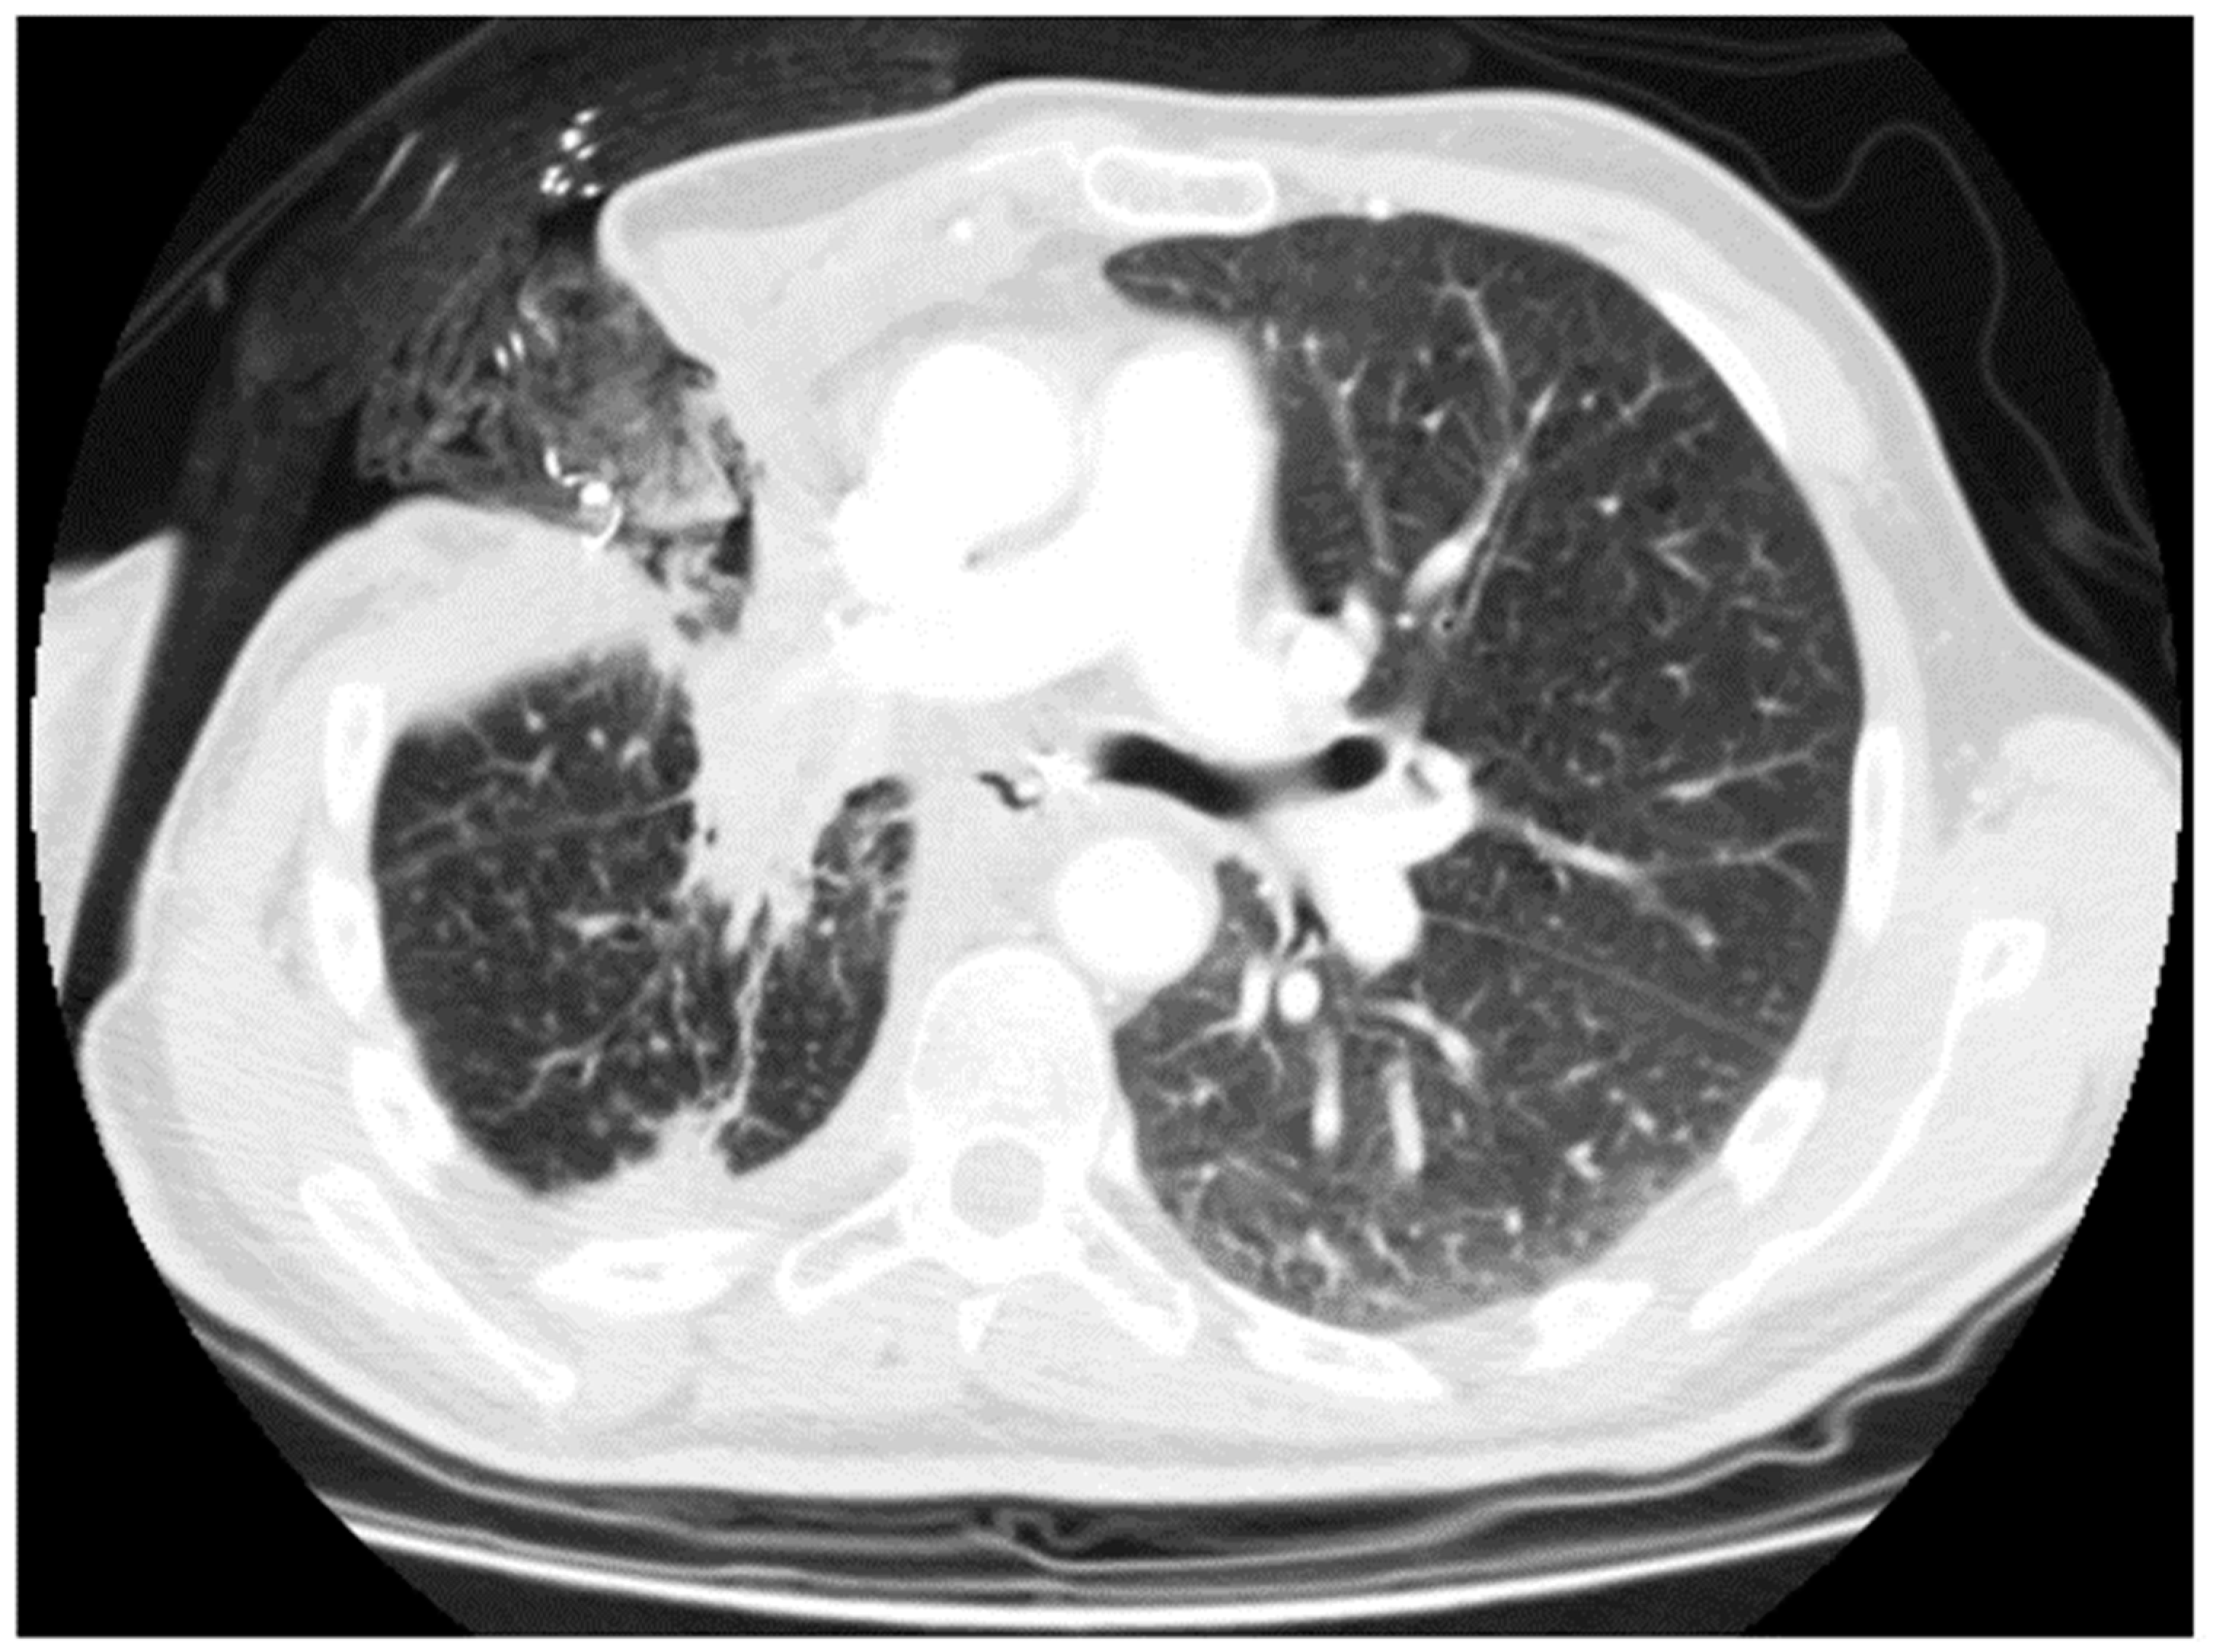

In the case of an unfit patient, small fistula, or small size of fluid–air collection, we opted for open window thoracostomy (OWT) (Figure 2 and Figure 3). The surgical technique of OWT has been widely discussed in our other papers [2,3].

Figure 3.

Open window thoracostomy after right upper lobectomy, after failure of bronchoscopic and minimally invasive approaches.

In this case, preoperative planning with computed tomography (CT) modeling is critical for performance of the OWT. Nevertheless, in the case of fistula after left upper lobectomy, we avoided OWT, because of the proximity of the arterial to the bronchial stump. This aspect could be crucial at a later stage, during future daily OWT medications, to avoid erosion by the gauzes on the arterial tissues, or broncho-arterial fistulas. In the case of a fit patient, large fistula, or large fluid–air collection, we preferred completion pneumonectomy [18,19,20]. In the case of BPF after completion pneumonectomy, we performed a classic OWT.

In 14 cases, a completion intervention (12 completion pneumonectomy, 1 tracheal sleeve pneumonectomy, and 2 extra middle lobectomy) was performed. In six cases, we performed OWT after lobectomy (Figure 2 and Figure 3); in eight cases, we performed OWT after completion pneumonectomy, complicated by fistula.

In our experience, we have seen that OWT post-lobectomy is an appropriate and safe choice (0% of 30-day and 90-day mortality), firstly making it possible to control the septic state, stabilize and improve the clinical status of the patients, and sterilize the cavity. In addition, it is helpful for the healing of the BPF and for the obliteration of the empyematic pleural space. On the other hand, OWT requires a considerable amount of time (months or years sometimes) for the total resolution of BPF, it needs daily medication, and it affects the patient’s daily quality of life. Finally, definitive closure of the OWT requires further surgical procedures.

A best evidence topic about the role of OWT after lung resection for lung cancer [26] reported that OWT can, in cases of failure of conservative treatments, represent a valid therapeutic tool in this group of patients. Regnard et al. [27] observed a success rate of OWT/muscle flap transposition in two out of four (50%) post-bilobectomy BPF and six out of seven (85.7%) post-lobectomy BPF, concluding that OWT is safe and effective in managing empyema post-pulmonary resection. Massera et al. [28] reported their experience with post-lobectomy (fifteen patients) or post-segmentectomy (four patients) empyema, treated by an immediate OWT followed by closure of the thoracostomy with a muscle flap within 5 months with no deaths. Sziklavari et al. [29] reported the results of 43 patients with pleural empyema, treated by VAC therapy with OWT, or mini-thoracotomy without rib spreading. All these studies considered pleural empyema with or without bronchial fistula and these results confirm the safety of the procedure but not the efficacy on late BPF. In our experience (five cases), first intention OWT made it possible to control the septic state and to completely resolve BPF. In the other three cases, the patients died before complete resolution of BPF, for completely independent reasons with respect to thoracostomy (cancer progression and one heart attack).